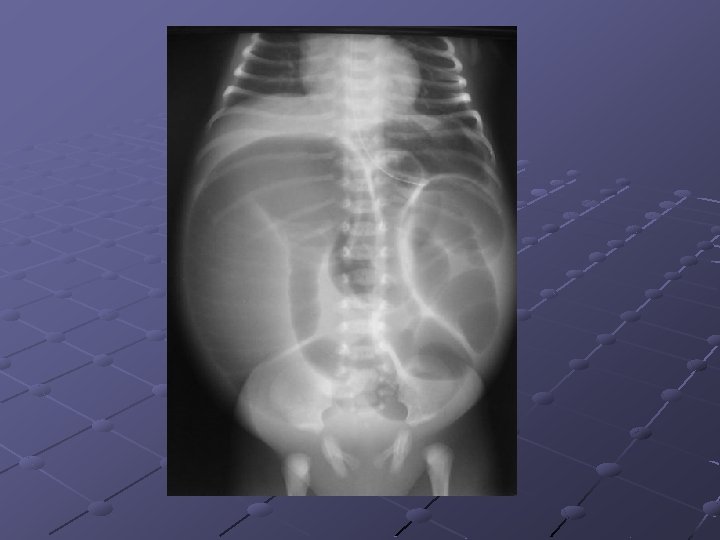

CAS N° 2 Absence d’émission du méconium Ballonnement depuis J 0 Bilan radiologique de J 2

Atrésie du grêle Interruption de la continuité intestinale Siège: duodénum (50%), jéjunum (35%) et iléon (15%) Facteurs fav évoqués: RCIU, consng. Infection maternelle, prise de cocaïne chez la femme enceinte… Prévalence: 0, 4 -2, 3 pour 10 000 Nces Théorie acceptée de nos jours: ischémie intestinale intra-utérine avec nécrose et résorption du segment concerné -thromboembolie -hypoxie fœtale -volvulus I-U -hernie interne -invagination intestinale aiguë